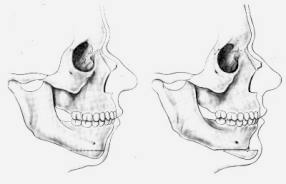

D’un point de vue plus global, il faut savoir que la position des sourcils est assurée par un équilibre entre deux forces opposées, constituées par des muscles abaisseurs (situés au voisinage des sourcils) et un muscle releveur (le muscle frontal).

Les rides horizontales sont dues à la contraction du muscle frontal qui est releveur. Les rides verticales inter-sourcilières sont occasionnées par la contraction des muscles abaisseurs.

‣ Pour les douleurs des articulations temporo-mandibulaires:

Le syndrome Algo-Dysfonctionnel de l’Appareil Manducateur (SADAM) parfois appelé syndrome de Cotten est une pathologie complexe dépendant de nombreux facteurs (occlusion dentaire, stress psychologique, pathologies articulaires, position cervicale…). De nombreux traitements peuvent être proposés (équilibration de l’occlusion dentaire, gouttière de libération occlusale, ostéopathie, posturothérapie, kinésithérapie, orthodontie, chirurgie orthognathique…). Dans certains cas, il peut y avoir un intérêt à agir directement sur les muscles qui compriment l’articulation temporo-mandibulaire.